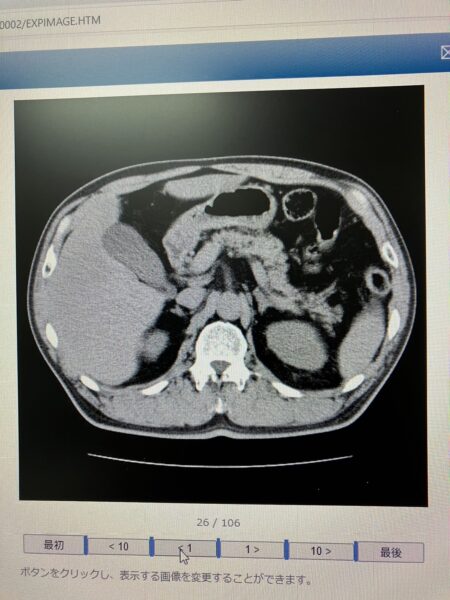

MRIの結果、脳には異状なし。

後にCTで膵臓もみたけど、他の臓器も異常なしで、